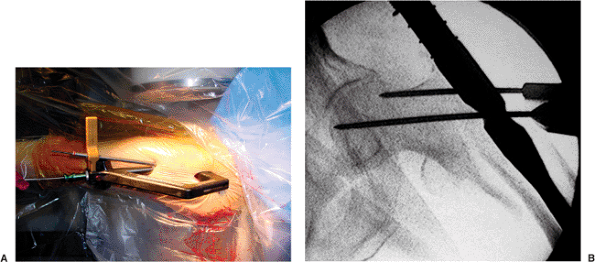

incision and subsequent lag-screw insertion, some systems have a tower

attachment that can be used to preview the position of the guide pin

for the sliding hip screw (Fig. 17.13A).

Through this positioning guide, a 3.2-mm guide pin can be placed

anterior to the patient’s soft tissue. Otherwise, one can estimate the

location and again inject with local anesthetic and make a 2-cm skin

incision. The surgeon should be certain to split through the fascia

lata so that the sleeve can be placed flush against the lateral cortex

of the femur (Fig. 17.13B). Taking into account

the anteversion of the neck, the surgeon should advance the appropriate

guide pin through the jig and nail up into the femoral head.

Figure 17.13. A. Tower attachment with guide pin allows preview of lag screw placement prior to skin incision. B. Jig assembly for guide pin placement into the head.

|